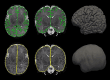

Figure 1

Cortical surfaces. Examples of the left and right hemisphere pial surfaces (green) and outer smoothed surfaces (yellow) used for calculation of the GI, overlaid on T2-weighted brain MRIs for one subject, acquired at 39+3 weeks. The surface renderings of both the pial and outer smoothed surfaces are shown alongside.